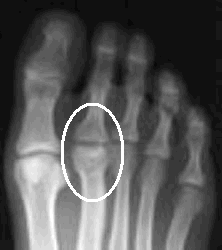

An x-ray may show a flattening of the bone in the early stages. At

this point, treatment may consist of a short leg walking cast and avoidance of

strenuous activity, including sports. The cast often stays on for three to

four weeks and eliminates the symptoms.